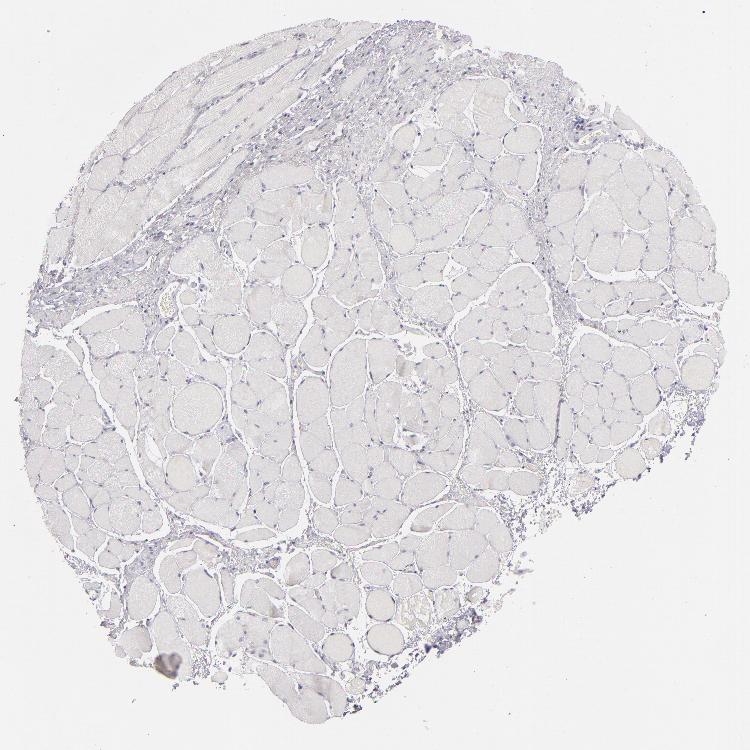

ESOPHAGUS - Antibody stainingi

Antibody staining in the annotated cell types in the current human tissue is reported as not detected, low, medium, or high, based on conventional immunohistochemistry profiling in selected tissues. This score is based on the combination of the staining intensity and fraction of stained cells.

Each image is clickable and will lead to virtual microscopy that enables deeper exploration of all samples and also displays staining intensity scores, fraction scores and subcellular localization as well as patient and tissue information for each sample.

Antibody CAB002221

Squamous epithelial cells Not detected